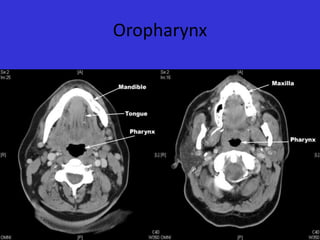

Oropharynx